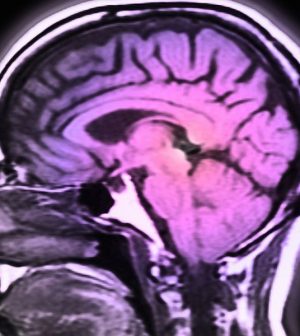

At issue are strokes caused by intracranial atherosclerosis, where blood vessels within the brain become hardened and narrowed.

Strokes occur when the blood supply to the brain is disrupted, depriving tissue of oxygen and nutrients. There can be various causes, and intracranial atherosclerosis is behind an estimated 10% to 15% of strokes in the United States, according to study author Dr. Nestor Gonzalez, a professor of neurosurgery at Cedars-Sinai Medical Center in Los Angeles.

Intracranial atherosclerosis is difficult to treat, Kim explained, because artery-clogging “plaques” may be scattered across the brain.

As neurosurgery goes, the approach is fairly simple and minimally invasive: a section of an artery in the scalp is re-routed to the surface of the brain. Over the next few weeks, new blood vessels begin to branch out from that artery into the brain, Gonzalez explained.

The idea is to supply better blood flow to areas of brain tissue at risk of stroke.